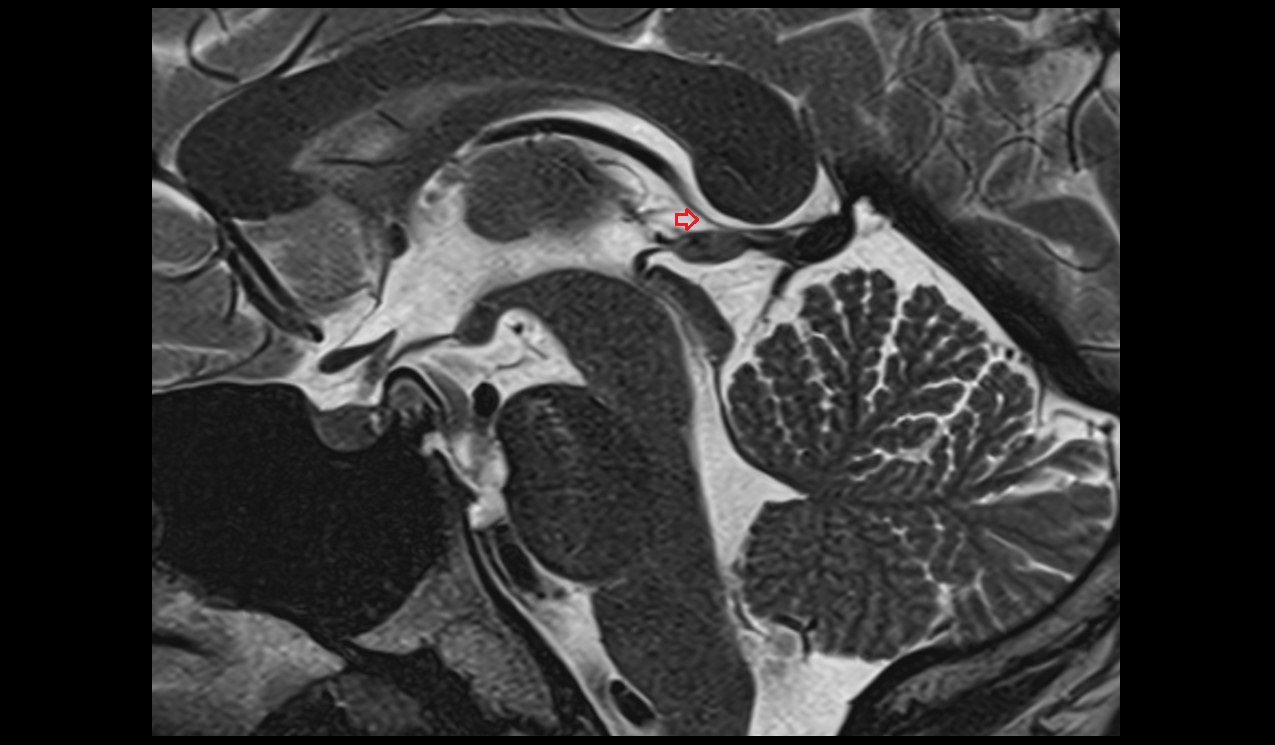

- Temporomandibular joint

- Articular disc of temporomandibular joint

- Articular eminence

- Mandibular condyle

- Mandibular fossa

- Superior head of lateral pterygoid muscle

- Inferior head of lateral pterygoid muscle